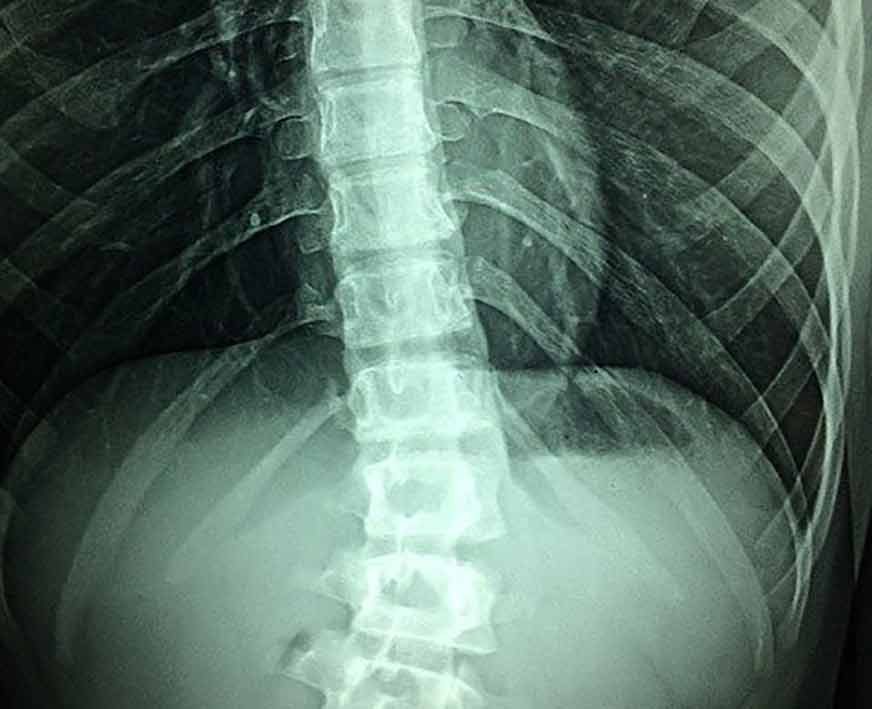

Osteopatia ed il male alla schiena

Il male alla schiena è una patologia oggi molto frequente, forse è quella che maggiormente spingerà il paziente verso la scoperta della osteopatia.

Esistono numerosi tipi di mal di schiena, questo soprattutto in base alla zona precisa che viene colpita come ad esempio la lombalgia, il mal di schiena a livello dorsale, o il dolore cervicale.

Una delle cause più comuni dei mal di schiena sono sicuramente generati da una cattiva postura, traumi che possono essere portati da cadute o incidenti, il dolore alla schiena è un blocco che si crea dalla poca mobilità muscolo-scheletrica, possono crearsi delle disfunzioni di tipo articolare, curve vertebrali non del tutto corrette: scoliosi, lordosi, cifosi, protrusioni oppure ernia del disco.

Anche un non corretto funzionamento degli organi interni può essere causa del mal di schiena, la relazione esistente tra la parte addominale e quella del rachide può essere causa di natura meccanica per una contrazione eccessiva della parte addominale, ma può essere anche di natura neurologica.